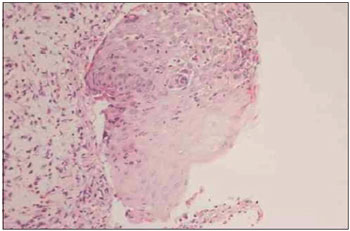

We performed an incisional biopsy of a lesion in the left buccal mucosa. The pathology results indicated mucositis with extensive erosion and the presence of a predominantly neutrophilic inflammatory infiltrate with degeneration and apoptosis of basal layer keratinocytes (Fig. 2). Direct skin immunofluorescence showed anti-IgA, anti-IgM, and anti-IgG linear fluorescence on the continuous dermal side of the cleavage (Fig. 3).

Figure 2. Predominantly neutrophilic inflammatory infiltrate with hydropic degeneration of the basal layer and apoptotic keratinocytes.